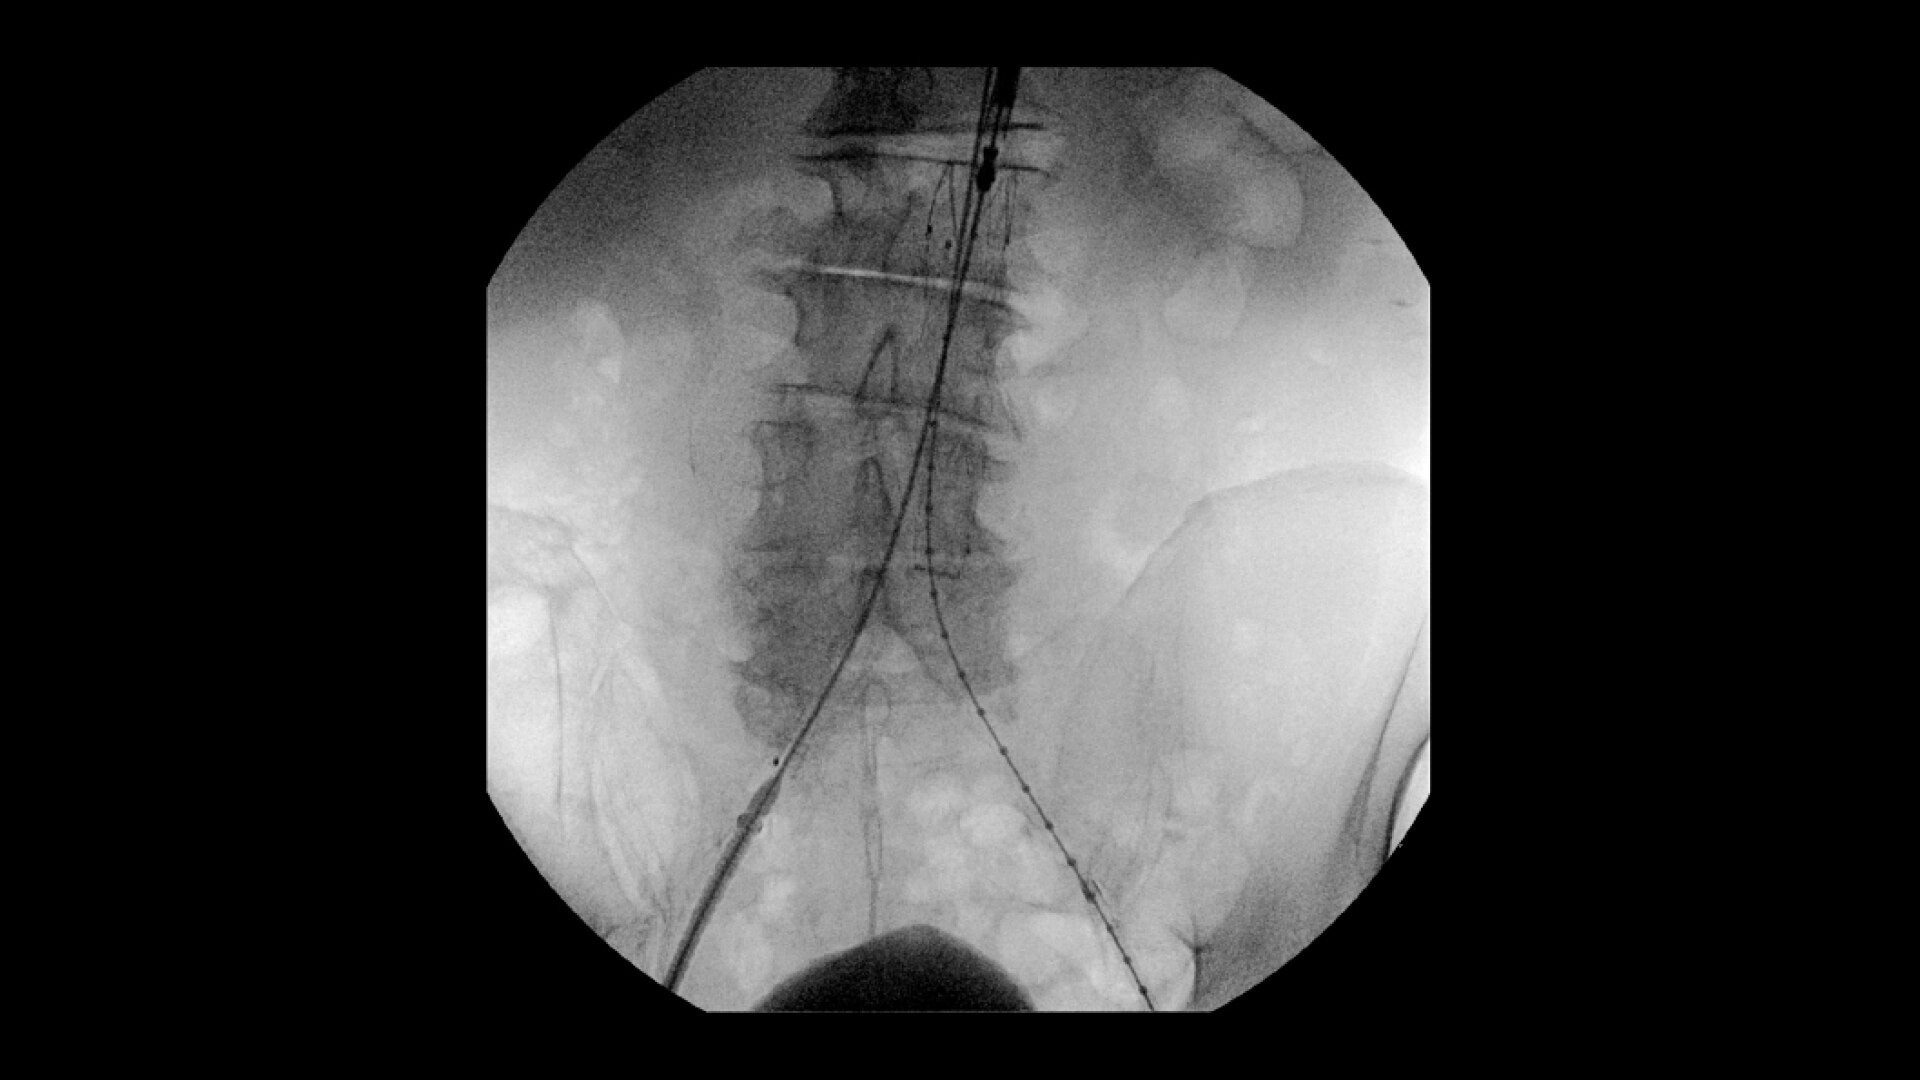

OEC C-arms are used by interventionalists and surgeons to obtain vascular imaging during peripheral to contrast run-off procedures. Superb resolution, even in the presence of motion, enables easy identification of anatomical landmarks and the extremity of the catheter, even as catheter tip moves.

Clearly see 0.014” guidewires in chest and abdomen region or 0.008” guidewires in peripheral vascular with the OEC Elite CFD with a flat detector, image processing advancements and 4K viewing display.

Experience fixed room-like images with eNR (enhanced Noise Reduction), an advanced software algorithm that automatically reduces image noise by 30% for an equivalent appearance of 30 kW power.

Perform a full leg Bolus Chase in one contrast run with a Preset Profile that includes Motion Tolerant Subtraction, that dynamically adjusts image quality based on presence of motion.

To see vessel stenosis or tips of guidewires, Live Zoom up to 4X during a fluoro or Cine without the additional dose of Mag modes or resulting X-ray tube heat buildup.

Complex vascular procedures require powerful imaging systems. OEC premium C-arms perform in a variety of procedures such as:

•Abdominal aortic aneurysm (AAA) stent and balloon deployment

• Infrarenal aortic aneurysm repair